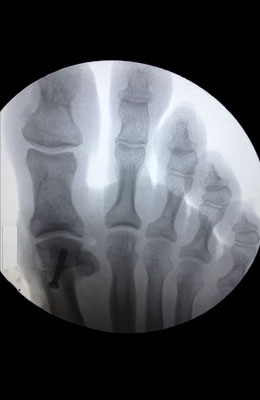

Before

Minimally Invasive Bunion Surgery before

After

Minimally Invasive Bunion Surgery after

Minimally Invasive Bunion Surgery featuring the miniBunon™ System and Tailors Bunionectomy

Melissa is a 32-year-old businesswoman who could not be off her foot post-surgery, yet she had a severely painful bunion. We performed our miniBunon™ System (our trademarked minimally invasive bunion surgery) and had a dramatic correction with no downtime. Melissa continued to work after her bunion surgery and was back in shoes and full activity at 5 weeks. Melissa could not believe the results of her Bunionectomy resulting in no bony bump, no scar and amazing motion. “After” picture taken immediately following surgery. Note the bunion and bunionette (Tailor’s bunion) in the before picture.